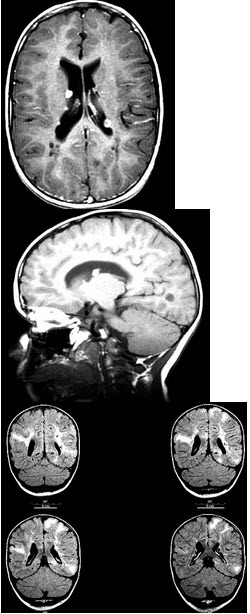

男性,7岁,癫痫间歇性发作三月余,面部有皮脂腺瘤,MR检查如图,最可能的诊断是( )

A:神经纤维瘤病

B:脑颜面部血管瘤病

C:脑囊虫病

D:结节性硬化

E:脑灰质异位